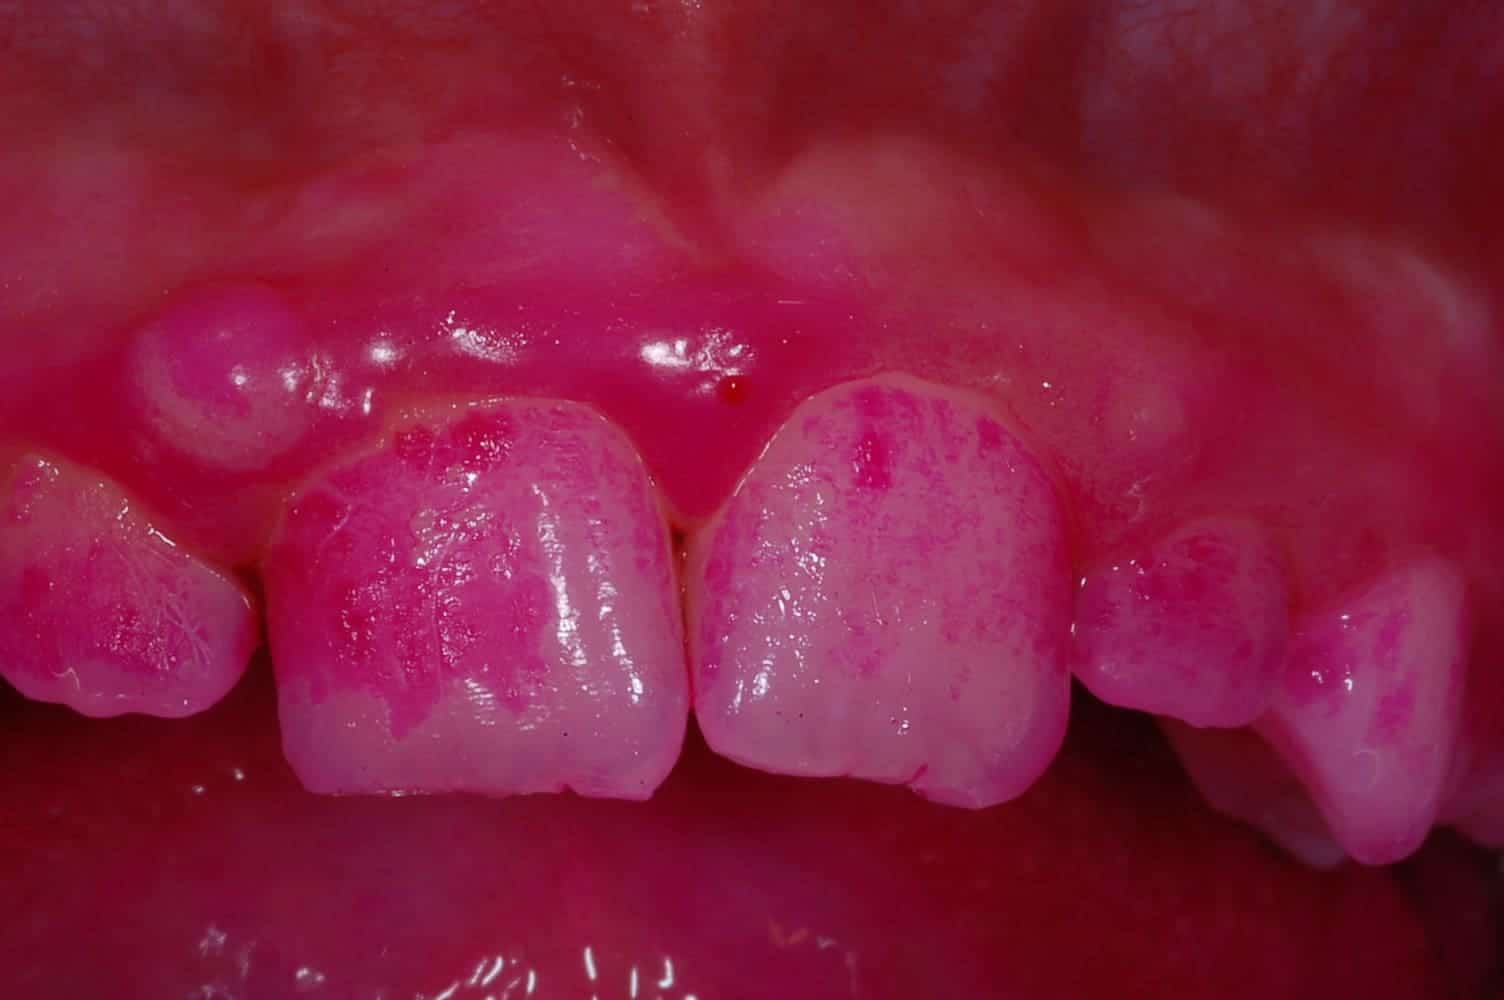

tecnica colorimetrica

Alimentazione e denti saniBlog

Indice di placca vs indice di massa corporea